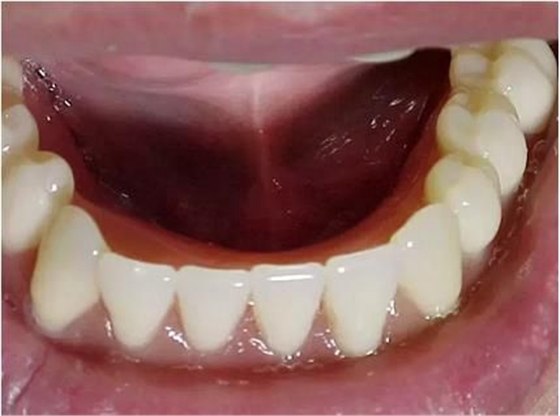

醫(yī)生在為患者制取印模之前,必須先對患者口腔的內(nèi)外環(huán)境進行一個系統(tǒng)的檢查,包括患者現(xiàn)有的義齒、牙槽嵴的情況、粘膜的情況、唇頰舌肌和舌體情況、顳下頜關(guān) 節(jié)的情況等等。通過觀察,醫(yī)生要明確印模的輪廓,未來基托以及牙列的輪廓。并且要在義齒設(shè)計單上標注有關(guān)的信息,讓技師的操作更明朗化。

尤其是口內(nèi)的檢查,應(yīng)當(dāng)仔細的檢查和觸診,對技師確定基托的范圍和厚度、需要緩沖和伸展的區(qū)域做明確的描述。

特別是有些牙槽嵴吸收嚴重的患者,此時患者的前庭顯得相當(dāng)?shù)膶挘t(yī)生應(yīng)當(dāng)記錄下見到的情景,讓技師在操作時做到心中有數(shù)。